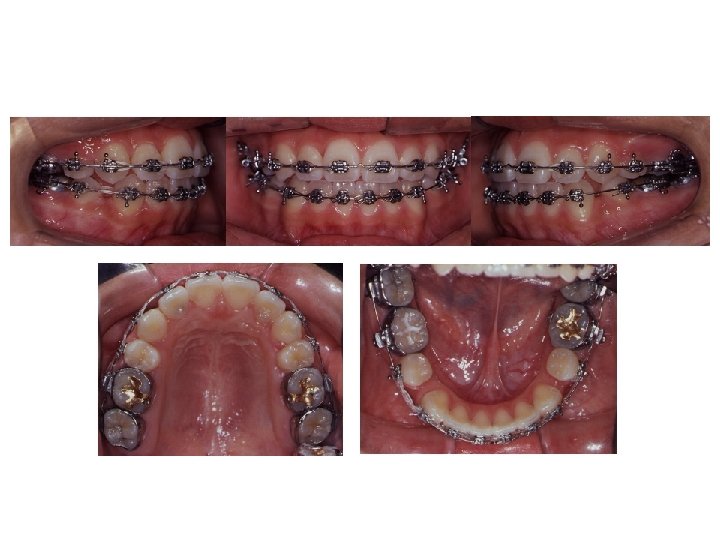

Final Intra-oral Photographs